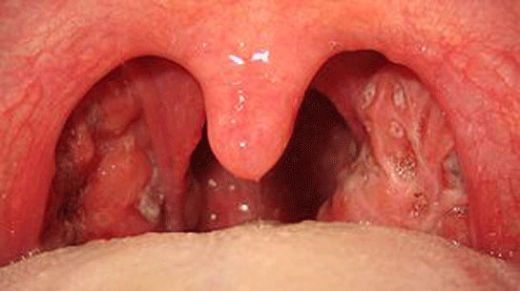

Sol bademcik şişmesi yaşadım ve gerçekten rahatsız edici bir durum. Boğazımda ağrı ve yutkunma güçlüğü ile birlikte beyaz lekeler oluştu. Tedavi için doktora başvurdum. Tek taraflı bademcik şişmesi doktor sitesinde de belirttiği gibi önemli bir durum, dikkat edilmesi lazım.

Alpartur, yaşadığın bu durum gerçekten de rahatsız edici olabilir. Boğazdaki ağrı ve yutkunma güçlüğü, günlük yaşamı olumsuz etkileyebilir. Beyaz lekelerin varlığı, enfeksiyon belirtilerine işaret edebilir ve bu nedenle doktora başvurman çok önemli bir adım.

Dikkat Edilmesi Gerekenler

Tek taraflı bademcik şişmesi, bazen daha ciddi durumların bir belirtisi olabileceğinden, doktorun önerilerini dikkatle takip etmekte fayda var. Özellikle ateş, şiddetli ağrı veya nefes alma zorluğu gibi belirtiler varsa, derhal sağlık kuruluşuna başvurmak gerekebilir.